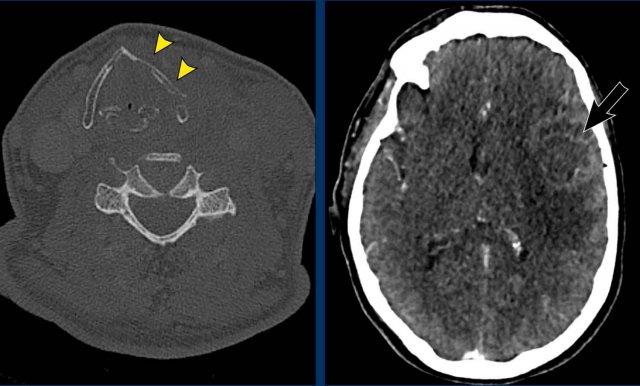

Ca lâm sàng

Hình ảnh của một bệnh nhân có khối u vùng cổ phát triển nhanh, với các triệu chứng khó nuốt và khàn tiếng.

Khám thực thể cũng phát hiện hội chứng Horner không hoàn toàn với sụp mi và co đồng tử.

Hình ảnh

CT đầu và cổ cho thấy khối u tuyến giáp xâm lấn với sự lan rộng cạnh thanh quản và trước cột sống, kèm theo xâm lấn sụn giáp (đầu mũi tên vàng).

Có huyết khối u trong tĩnh mạch cảnh (mũi tên đen).

Continue with the next images…

Lưu ý sự xâm lấn sụn giáp (đầu mũi tên màu vàng).

Ở rìa của lát cắt có một di căn não.

Thảo luận

Hội chứng Horner xảy ra do ảnh hưởng đến hệ thống hạch trước.

Có nhiều sợi thần kinh kết nối hạch cổ giữa (MCG) và hạch cổ dưới (ICG), nằm ở phía trước và phía sau động mạch đốt sống.

Chẩn đoán cuối cùng

Ung thư tuyến giáp thể không biệt hóa.

Đây là một trong những khối u ác tính hung hãn nhất và có tiên lượng xấu.